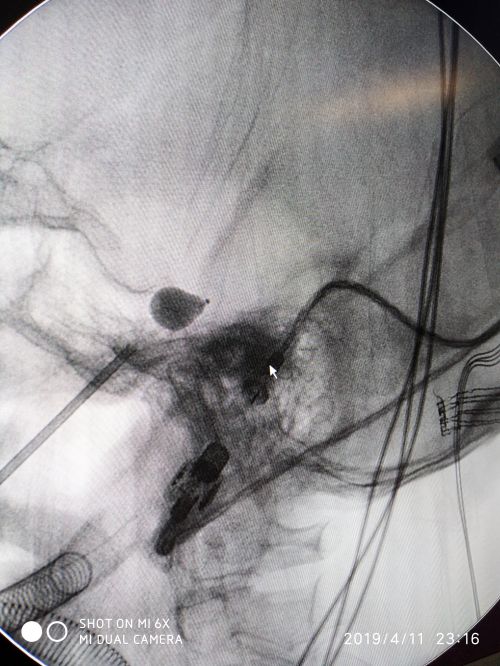

c臂引导下经皮三叉神经半月节微球囊压迫术。

术中影像学定位与球囊理想“梨形”填充。